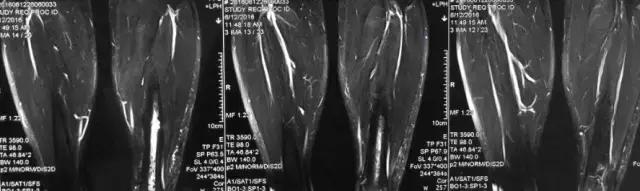

核磁示中下段骨髓炎,上面切口处流脓,请问张主任你的意见要上手术吗?

北京积水潭医院张伯松:

1、是具备手术指征了!也就是说可以手术。 2、并不是必须马上手术。不发热,不红肿、化验都正常也可以换药口服抗生素。